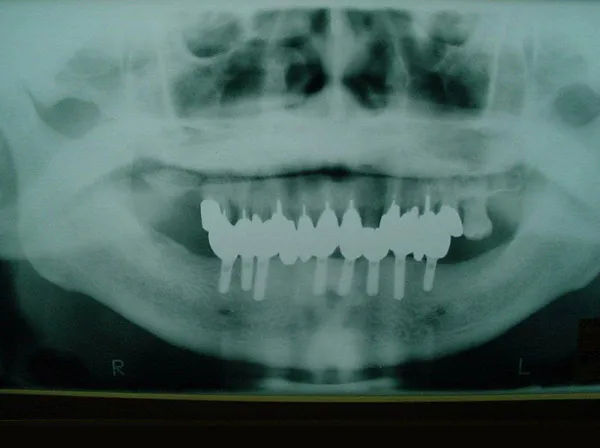

写真3のレントゲン写真で、下顎の骨の中に8本のインプラントが確認できます。

写真5のレントゲン写真で、8本のインプラント下部構造の上に、11歯分の冠が装着されている様子が確認できます。